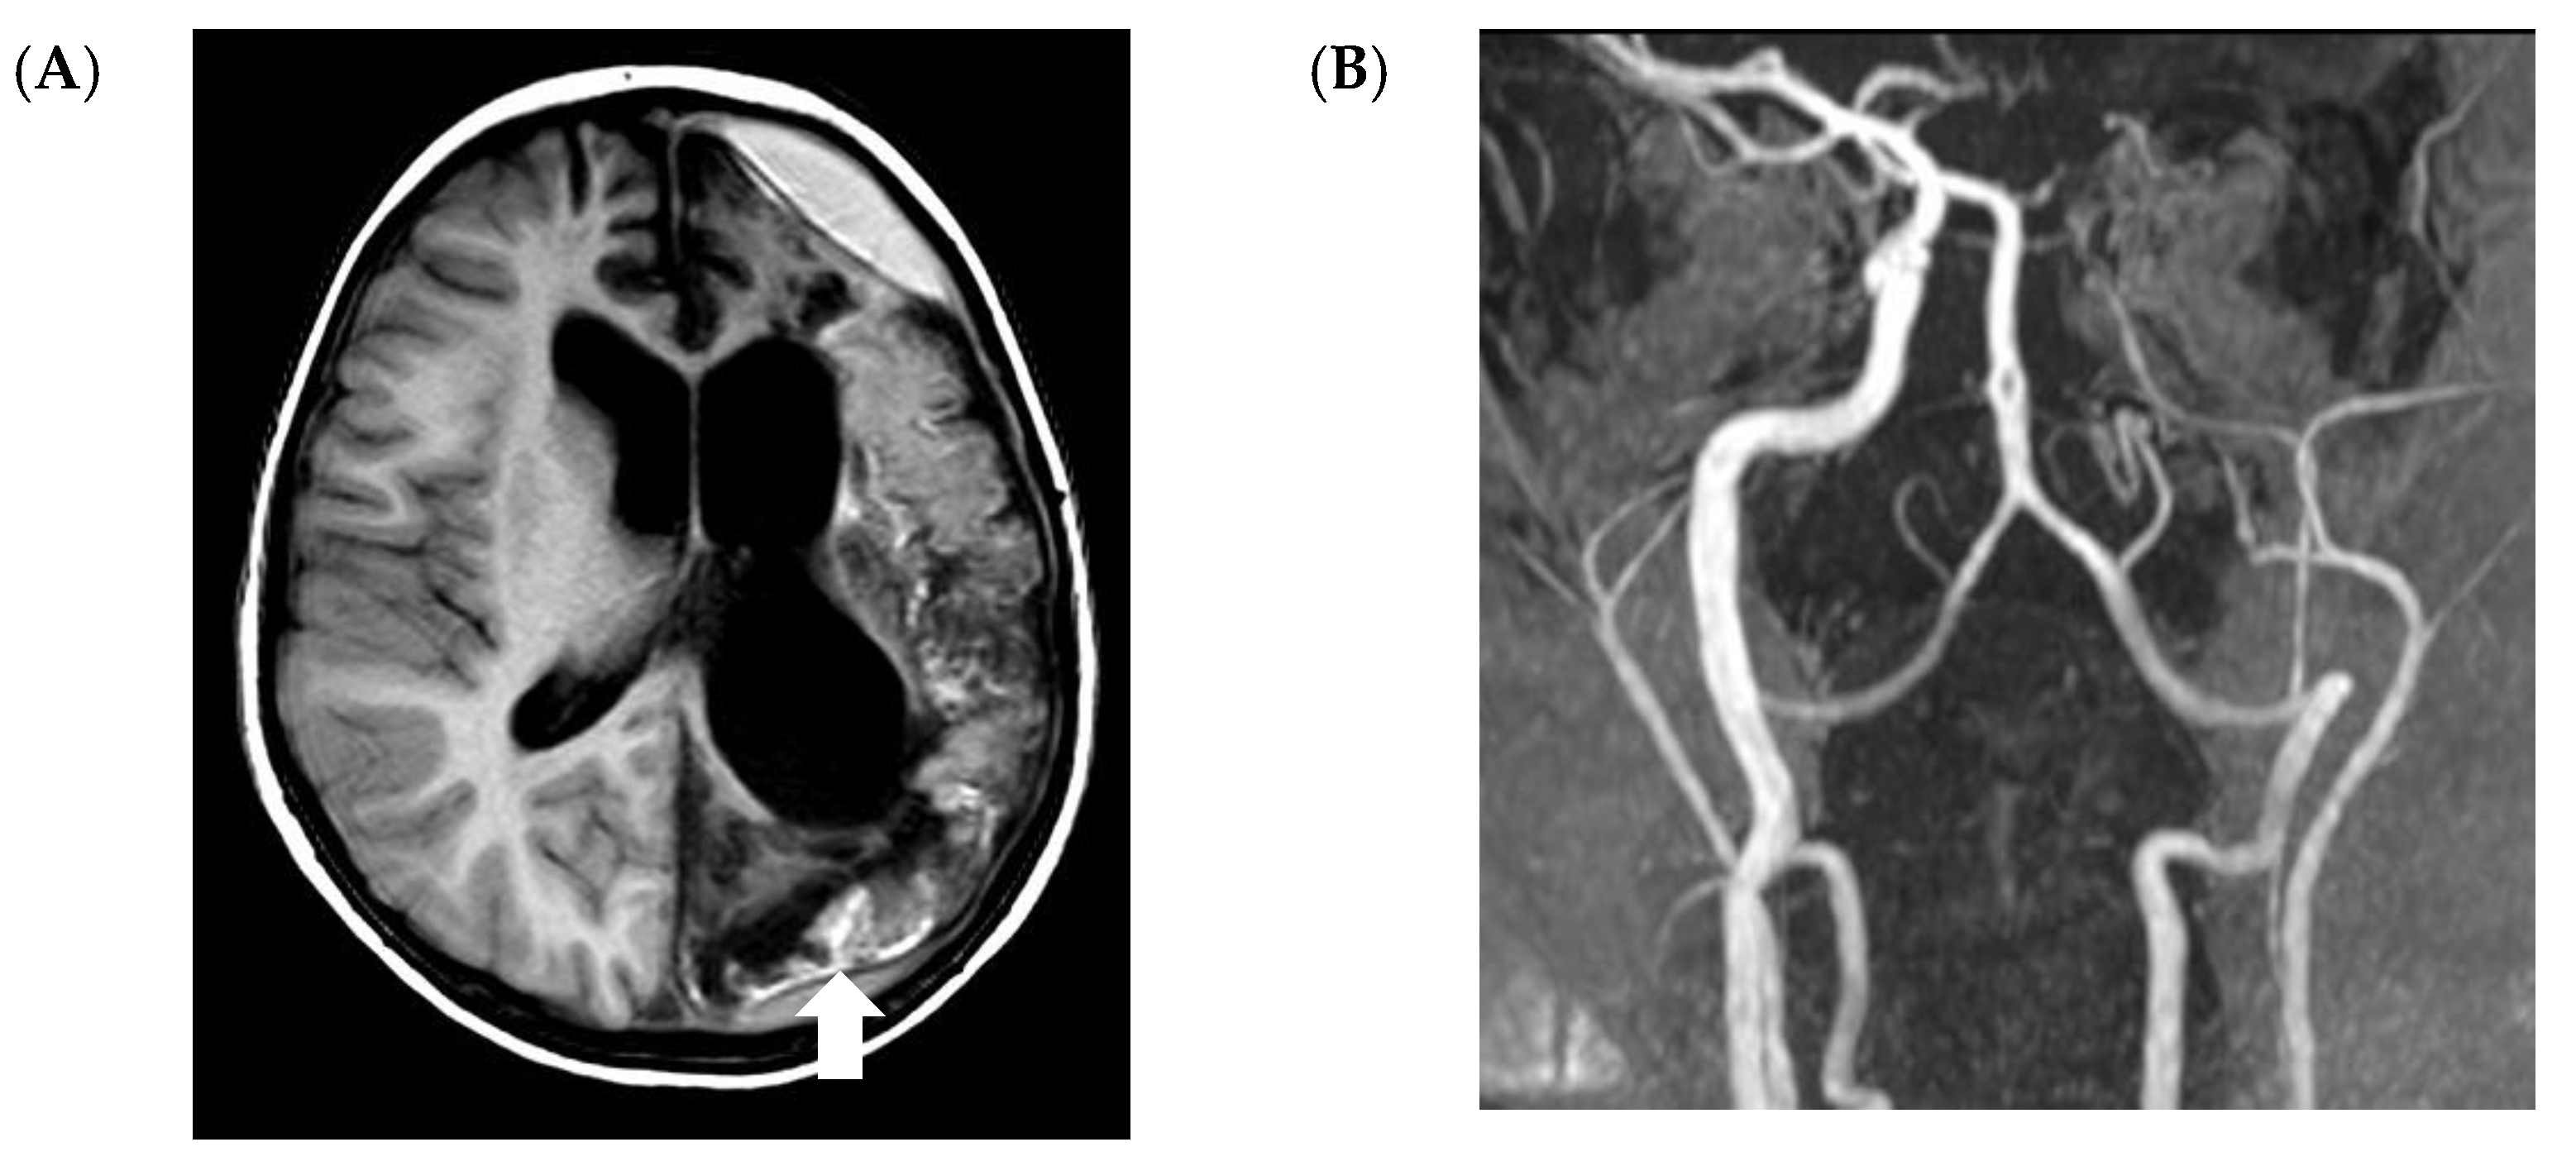

5.2. CNS Manifestations

- Nickerson, J.P.; Richner, B.; Santy, K.; Lequin, M.H.; Poretti, A.; Filippi, C.G.; Huisman, T.A. Neuroimaging of pediatric intracranial infection--part 2: TORCH, viral, fungal, and parasitic infections. J. Neuroimaging 2012, 22, e52–e63. [Google Scholar] [CrossRef] [PubMed]

- Gavito-Higuera, J.; Mullins, C.B.; Ramos-Duran, L.; Olivas Chacon, C.I.; Hakim, N.; Palacios, E. Fungal Infections of the Central Nervous System: A Pictorial Review. J. Clin. Imaging Sci. 2016, 6, 24. [Google Scholar] [CrossRef]

- Ashdown, B.C.; Tien, R.D.; Felsberg, G.J. Aspergillosis of the brain and paranasal sinuses in immunocompromised patients: CT and MR imaging findings. AJR Am. J. Roentgenol. 1994, 162, 155–159. [Google Scholar] [CrossRef]

- Antulov, R.; Dolic, K.; Fruehwald-Pallamar, J.; Miletic, D.; Thurnher, M.M. Differentiation of pyogenic and fungal brain abscesses with susceptibility-weighted MR sequences. Neuroradiology 2014, 56, 937–945. [Google Scholar] [CrossRef]

- Mathur, M.; Johnson, C.E.; Sze, G. Fungal infections of the central nervous system. Neuroimaging Clin. N. Am. 2012, 22, 609–632. [Google Scholar] [CrossRef]